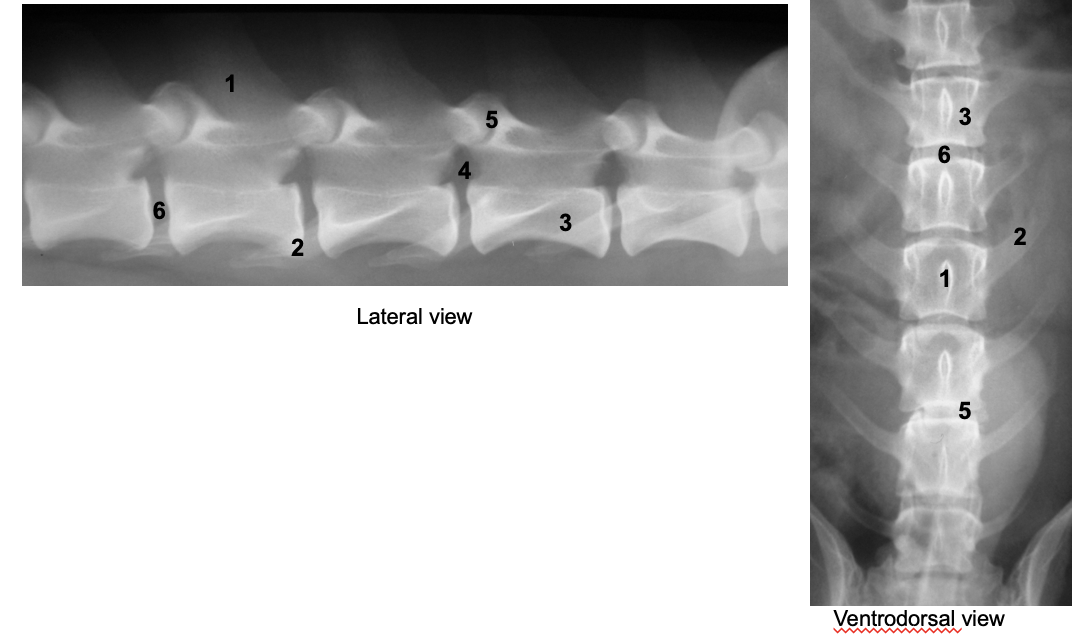

what are the most radiographic views taken of the vertebral column

what are the labelled parts

superimposition

the dorsal spinous processes can be seen in lateral view but are superimposed in ventrodrosal

transverse processes can be seen in ventrodorsal view but less in lateral